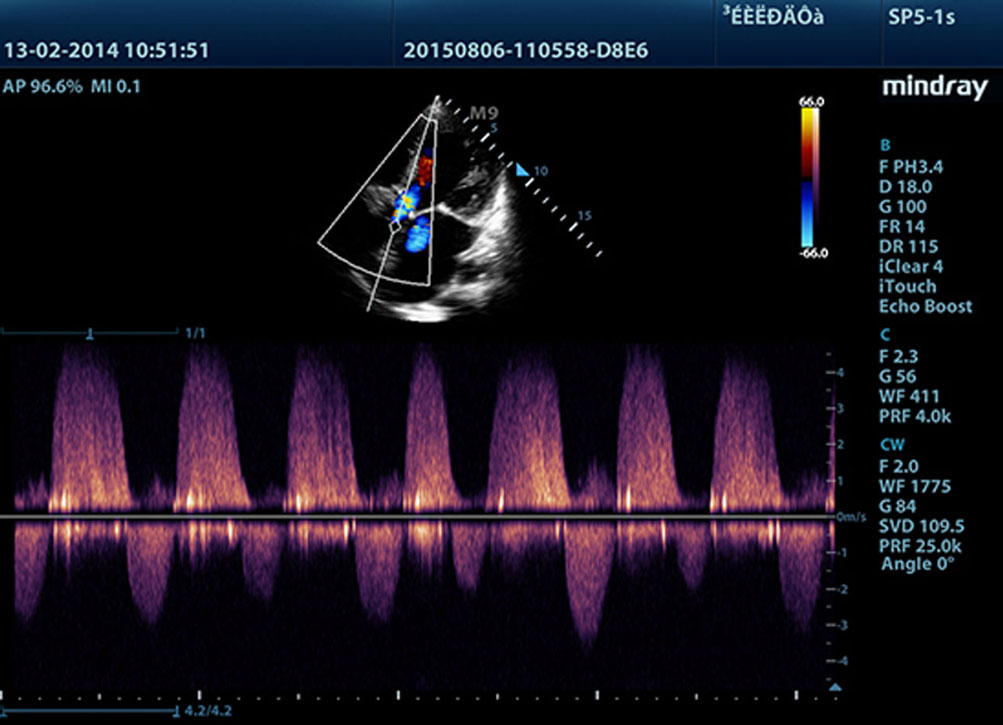

LVO with Stress Echocardiography

M9ŌĆÖs premium capabilities allow for LV opacification during stress, enhancing discrimination between myocardial tissue and blood pool, providing better visualization of the endocardial surface. Stress Echo feature on M9 includes a complete package for pharmacological stress and exercise stress echo. The package is supported by a flexible reporting system that can be optimized for your individualistic needs.